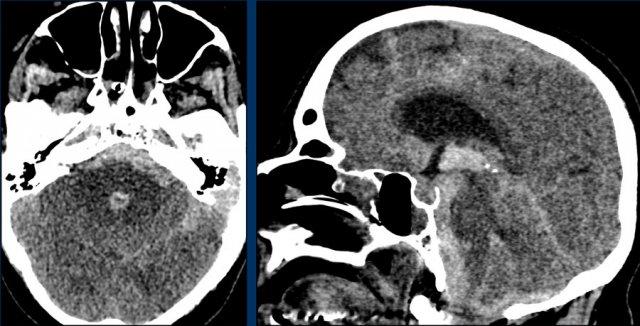

Đây là một ví dụ về xuất huyết dưới nhện trên NECT.

Lưu ý vị trí máu chủ yếu xung quanh thân não và trong não thất III và IV.

Thông thường, vị trí của máu dưới nhện giúp định hướng xác định vị trí của túi phình động mạch.

Bước tiếp theo là thực hiện chụp CT mạch máu (CTA) để tìm kiếm túi phình động mạch là nguyên nhân gây SAH.

Bệnh nhân này có túi phình tại nguyên ủy của động mạch tiểu não sau dưới trái (PICA).

Cũng cần lưu ý tình trạng não úng thủy.

Bệnh nhân này được thực hiện chụp mạch số hóa xóa nền (DSA) và sau đó được nút coil.

DSA cho thấy một túi phình hình túi của PICA trái, đường kính tối đa 6 mm với cổ ngắn và hẹp.